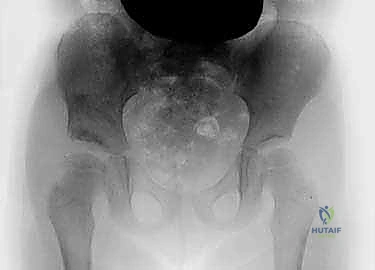

قبل دخول غرفة العمليات، يتم دراسة صور الأشعة السينية والمقطعية (CT Scan) للطفل بدقة، وتحديد زوايا القطع العظمي المطلوبة بالملليمتر.

باستخدام أدوات جراحية دقيقة جداً، يتم إجراء القطع العظمي في الحوض وثني سقف الحُق لتغطية رأس الفخذ بالزاوية المثالية التي تم التخطيط لها.